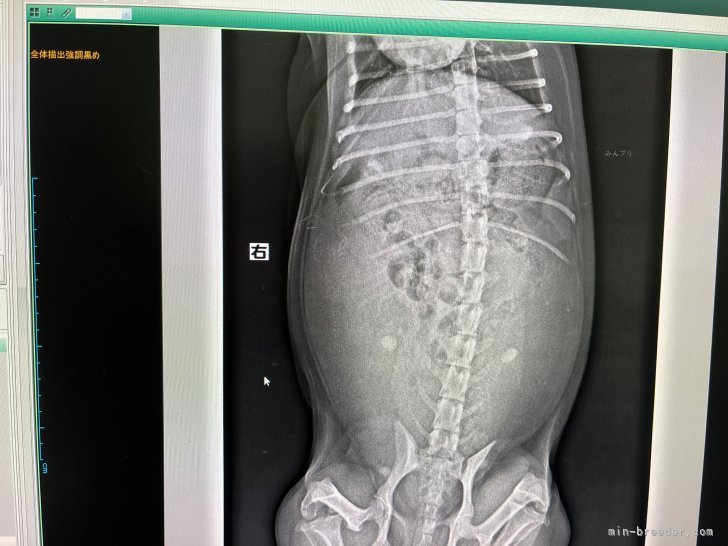

出産直前のレントゲン検査結果🐶本日、くうちゃん出産直前の最終レントゲン検査 行ってきました🐶 結果… 3頭は確...